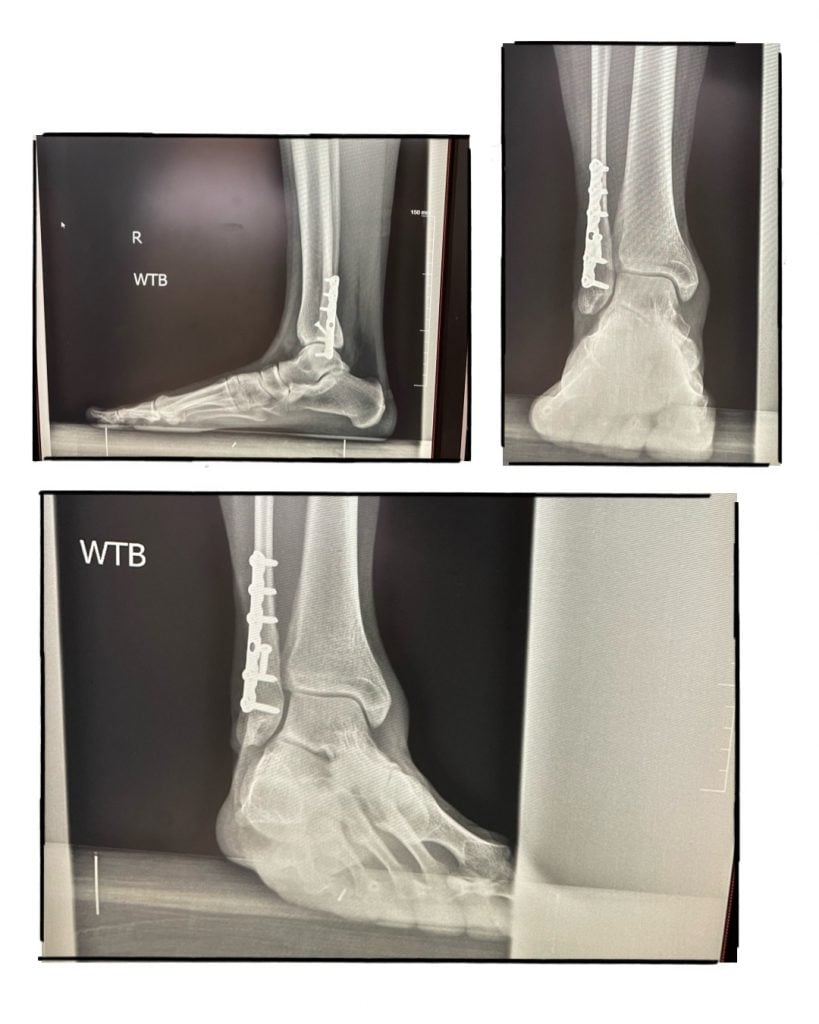

On May 25, 2010, I survived a head-on collision on Route-87. An 89-year-old man with dementia crossed over the meridian and hit me head on. After paramedics took 1 1/2 hours to free me from the vehicle, I was air lifted to a facility in Westchester, who wanted to amputate my lower right leg. At this facility, I had 2 surgeries there to "clean out" the right tibia and leg. My ankle was crushed from the accident. When I was there, I called my friend to help me. My friend, who used to be a PA at HSS, recommended me to Dr. Helfet, who eventually saved my leg after 3 surgeries. I consider him to be the Guru of orthopedic surgeons. Six months after the surgeries, I was back in high heels. Soon after that, I could hike mountains. If it was not for Dr. Helfet and HSS, I would not be where I am today.